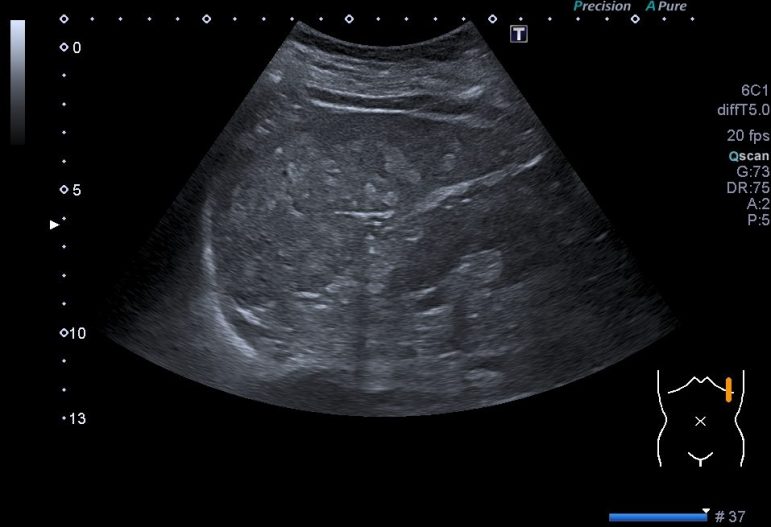

Observas, semiólogicamente hablando, un bazo con una gran cantidad de lesiones ocupantes de espacio, hiperecogénicas que afectan a toda la ecoestructura. Doppler normal.

Compara normalidad y patología. Cuando vi este bazo me asusté, pensé que era otra cosa y avisé al radiólogo inmediatamente, saltaron mis alarmas, pero finalmente se comprobó que la sarcoidosis ya era conocida y que mi miedo era infundado. Siempre que veamos anormalidad, debemos tener en cuenta las líneas rojas, lesiones nodulares sólida ocupantes de espacio en órganos compactos del abdomen, pueden ser una de estas líneas rojas y estas deben ser comentadas siempre con el radiólogo responsable.